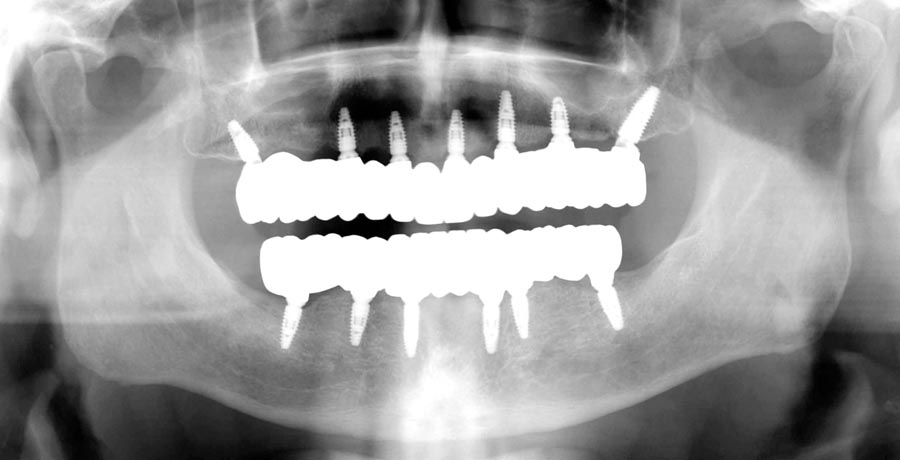

Smile GalleryImplant RestorationsFull Mouth Implant Restoration 1 of 13 Pre-operative smile Pre-operative smile Pre-operative frontal view, lips retracted Pre-operative panoramic image (note bone levels) Post-surgical panoramic image Surgical temporary bridge (note convex contours) Delivery of surgical temporary bridges in both upper and lower Two weeks post-op surgery and temporaries (note amazing tissue response) Three months post- surgery. (Note tissue development) Definitive implant bridges (FP-2) Post-treatment panoramic image Final result smile Final result smile